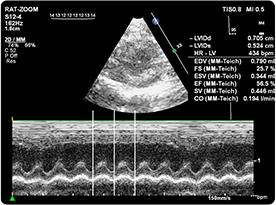

超聲成像技術(shù)是利用超聲波的物理特性和動物體器官組織聲學特性相互作用后產(chǎn)生的信息,經(jīng)信息處理形成圖像的成像技術(shù)。

動物體結(jié)構(gòu)對于超聲而言是一個復(fù)雜的介質(zhì),各種器官與組織(包括病理組織)都有它特定的聲像阻抗和衰減特性,因而構(gòu)成聲阻抗上的差別和衰減上的差異,這種不同的反射與衰減構(gòu)成了超聲圖像的基礎(chǔ)。因而根據(jù)顯示和記錄的波形、曲線或圖像的形式,借以進行集體的檢查和疾病的診斷。

| 超聲儀(含氣麻費用) | 450 | 元/只/次,單次5只起做 | 心超(射血分數(shù)EF,縮短分數(shù)FS,收藏末期直徑LVESD、舒張末期直徑LVEDD、收縮期容積LVVS、舒張期容積LVVD) |